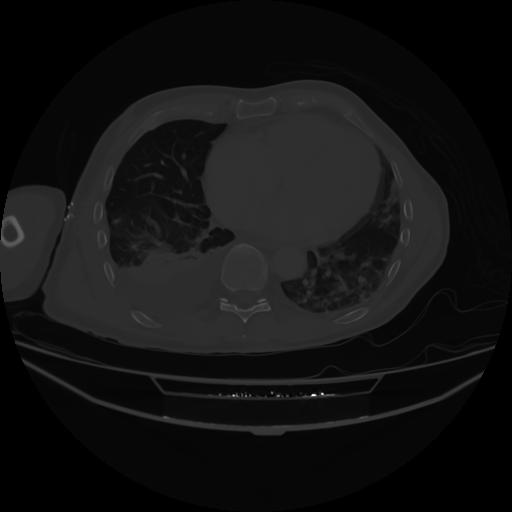

4 CUERPO,CE,Axial,3.0,CUERPO,,